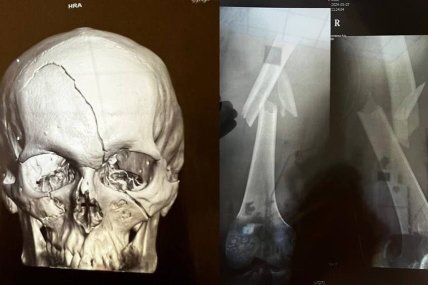

У прифронтовій зоні п’яний чоловік нібито збив бійців батальйону "Айдар", внаслідок чого вони зазнали тяжких поранень. Інцидент стався під час комендантської години.

"Як розповідають самі захисники, сталася ДТП ще й під час комендантської години. Військові отримали тяжкі травми, проте водій досі має посвідчення водія і продовжує їздити на авто", — йдеться в публікації.